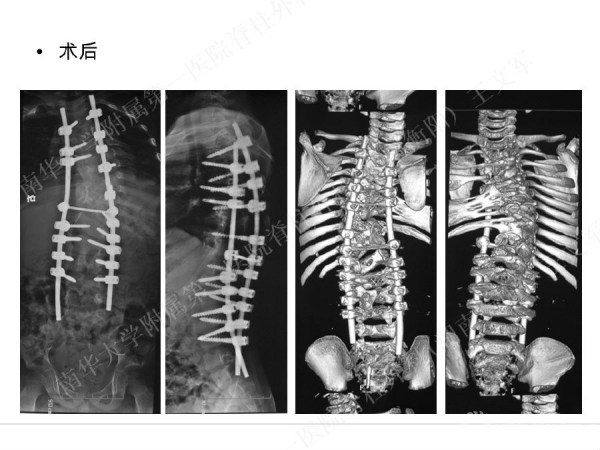

拥有完全自主知识产权的滑槽钉生长棒非融合技术,由南华大学附属第一医院脊柱外科王文军教授研发。

该技术在提供良好矫形固定效果的同时,保留了脊柱生长潜能、尽可能减少对患儿脊柱生长的影响,初步临床效果显示该系统是简单安全有效的,是严重儿童早发脊柱侧弯矫形治疗的一种有益尝试。

擅长脊柱脊髓疾病的微创及非融合手术治疗,目前率领科室开展的先进微创手术有:椎间孔镜技术、经皮穿刺腰椎外固定支架术治疗胸腰椎骨折、腹腔镜下人工腰椎间盘置换术、胸腔镜下胸椎前路手术、腰骶椎轴向融合术。率先在全国业界提出组合微创技术的理念,大大提升了脊柱微创技术的应用范围和治疗效果。拥有自主知识产权的生长棒技术在早发性脊柱侧弯术中的应用解决了儿童脊柱侧弯既早期矫形,又不影响生长发育的世界性难题。